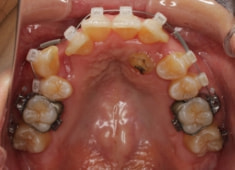

症例紹介

左上3番埋伏歯

治療法:フルパッシブブラケット:T21

治療開始時